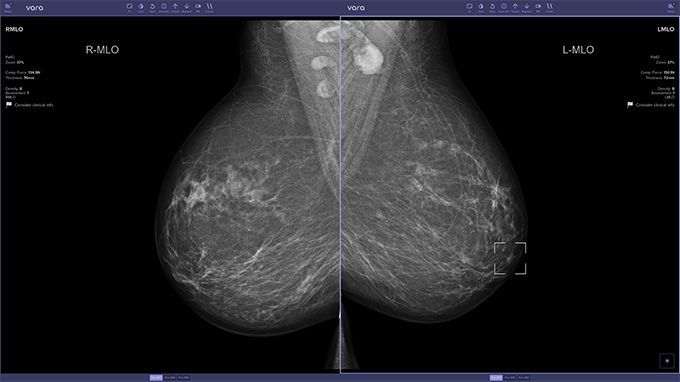

To see if AI could lighten the load, decision referral software was installed at 12 screening sites across the country. More than 460,000 women ages 50 to 69 took part in the study from July 2021 through late February 2023. AI tagged the mammograms as normal, suspicious or unclassified. The 119 participating radiologists chose to use an AI-supported image viewer, which revealed the software’s assessment, for roughly half of the women’s screenings.

How the AI would best fit into radiologists’ workflow remains an open question, but it could replace one of the initial readers, says Stefan Bunk, chief technology officer and cofounder of Vara, the health care technology company in Berlin that developed the AI. “This discussion should now start.”